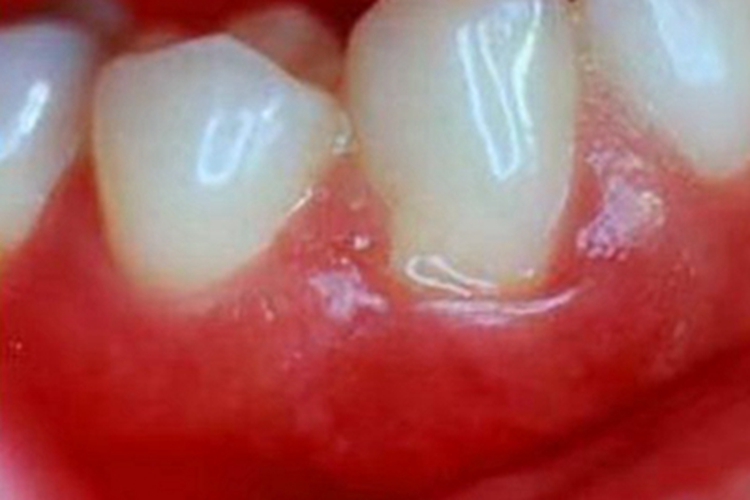

牙龈炎可导致牙龈发红、充血或肿胀,呈鲜红色,表面较为光滑、透亮,一般无疼痛,咀嚼食物时可有不适感。

当口腔中的细菌和食物残渣在牙龈和牙齿表面形成牙菌斑时,细菌会产生毒素和代谢产物,刺激牙龈组织引发牙龈炎。炎症会导致牙龈的血管扩张和通透性增加,血管壁变薄,血流量增加。这一过程导致牙龈充血,血管渗漏,使得局部组织充满液体和红细胞,出现肿大和充血的现象。